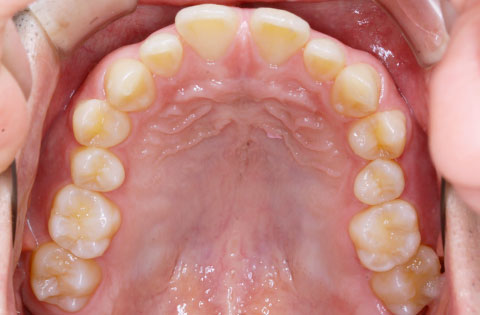

矯正前 上顎

矯正後 上顎